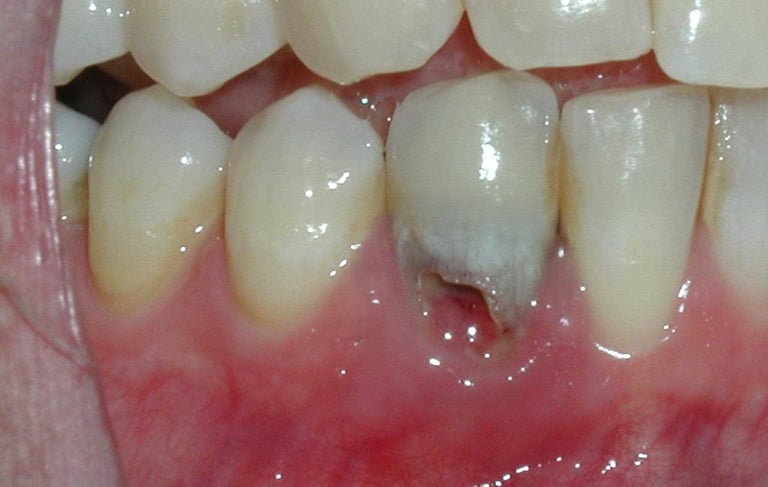

Se revisa si hay fracturas en la parte visible del diente. Las fracturas de la corona pueden ser causadas por trauma o caries extensas y pueden afectar el tratamiento endodóntico.

Evaluación de fracturas de la corona

Se detecta cuando el cuerpo empieza a descomponer el tejido óseo de la raíz del diente, lo que puede ser causado por trauma o enfermedades. Se requiere diagnóstico por imagen y evaluación clínica.

Diagnóstico de reabsorción radicular